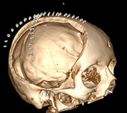

Demolizione/ricostruzione

cranica in un unico tempo |

| Meningioma

con demolizione-ricostruzione della teca cranica in un unico tempo

con tecnica microchirurgica e neuronavigazione. |